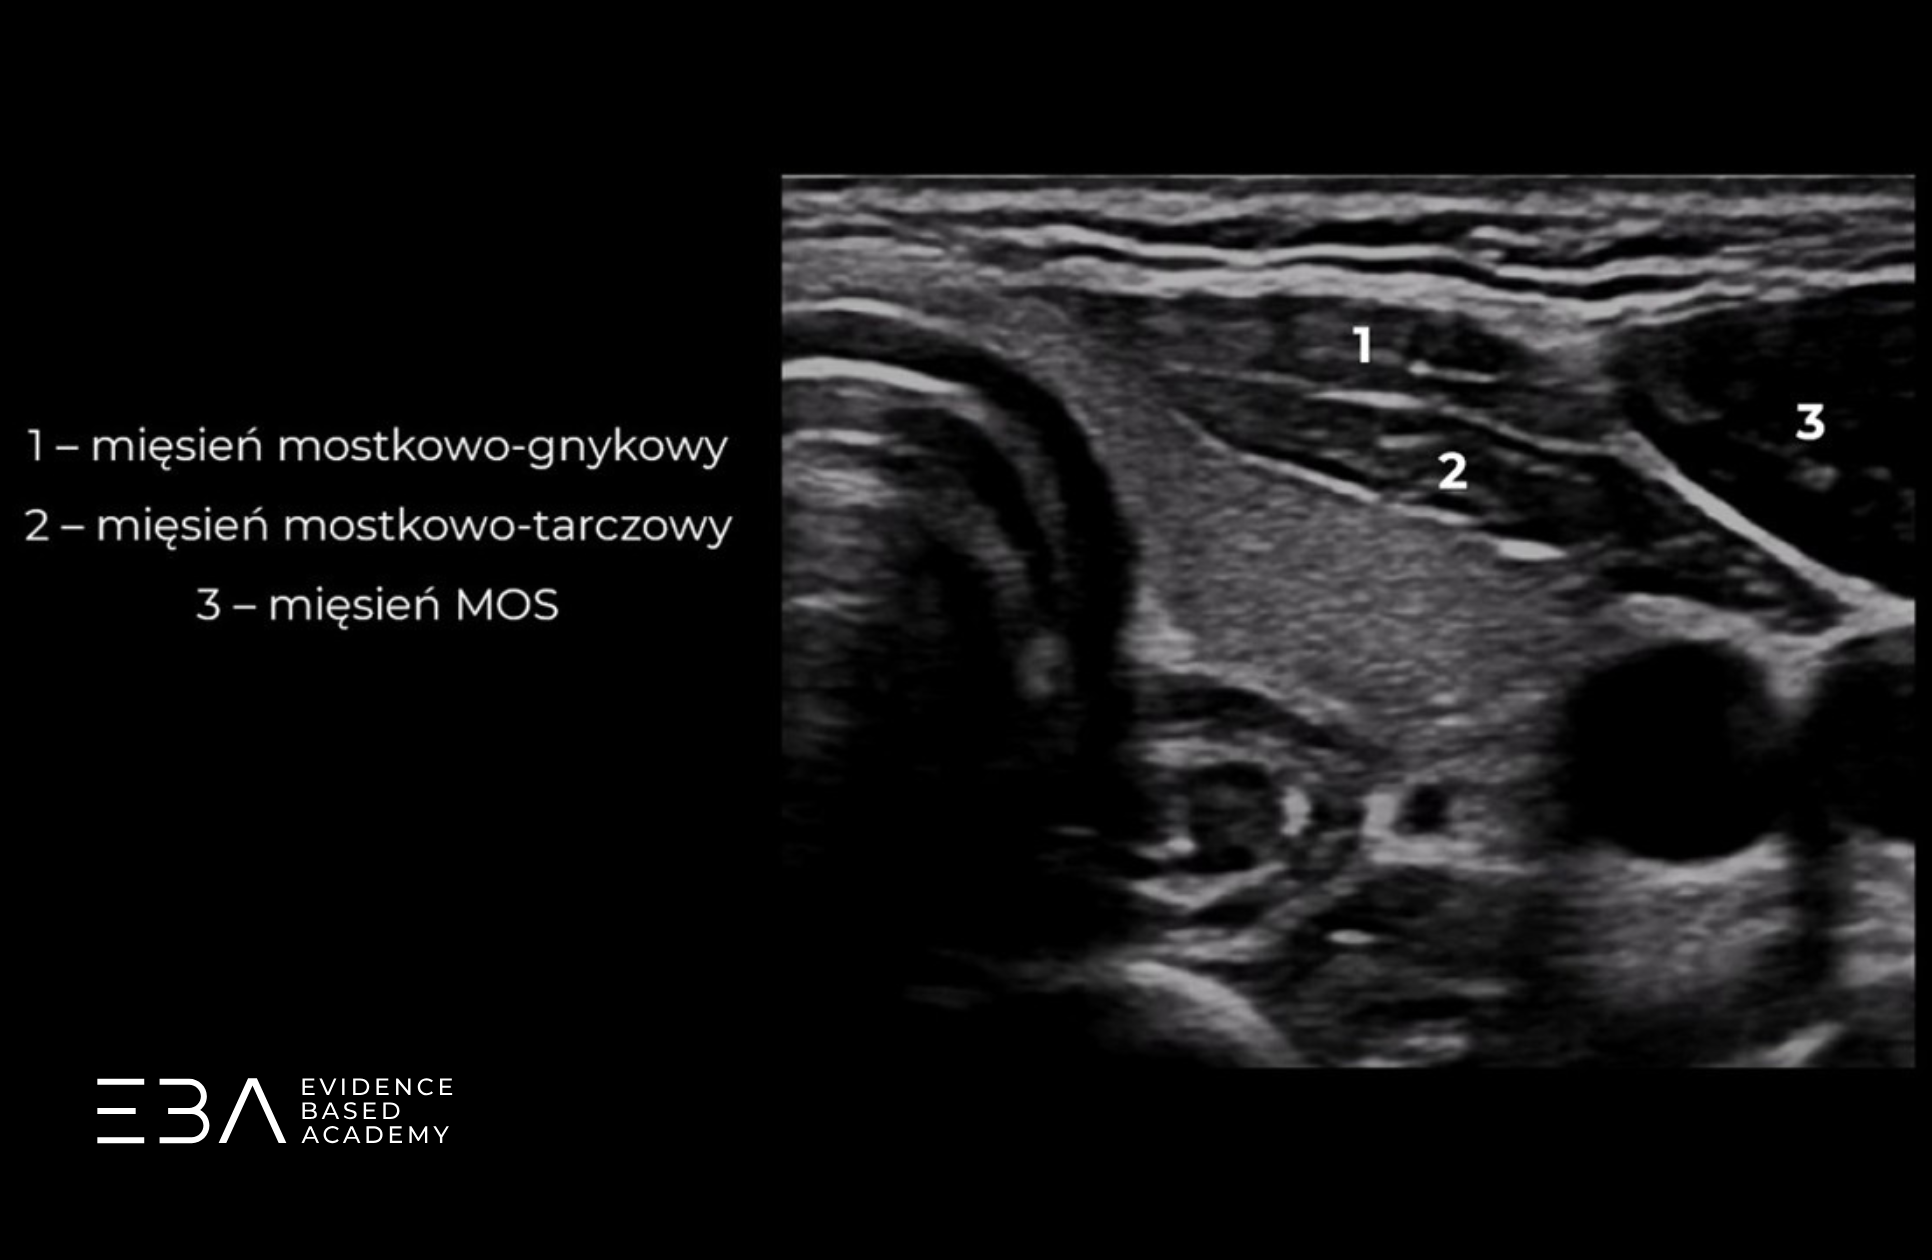

Struktury, które musimy zidentyfikować i ocenić, to: język, ślinianki podjęzykowe, kość gnykowa, mięsień mostkowo-obojczykowo-sutkowy (MOS) oraz grasica. Jest to istotna część badania tarczycy, ponieważ pozwala nam na wykrycie potencjalnych wad rozwojowych oraz wariantów anatomicznych związanych z rozwojem tarczycy i innych narządów szyi.

Echogeniczność miąższu tarczycy oceniamy względem echogeniczności otaczających ją mięśni (mięśni podgnykowych i MOS). Prawidłowa echogeniczność miąższu tarczycy jest wyższa od echogeniczności otaczających mięśni i jest taka sama w każdej jej części.